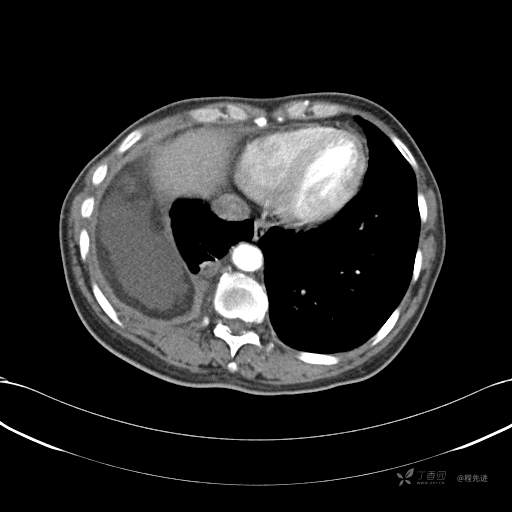

患者性别:女

患者年龄:51岁

简要病史:胸闷半年